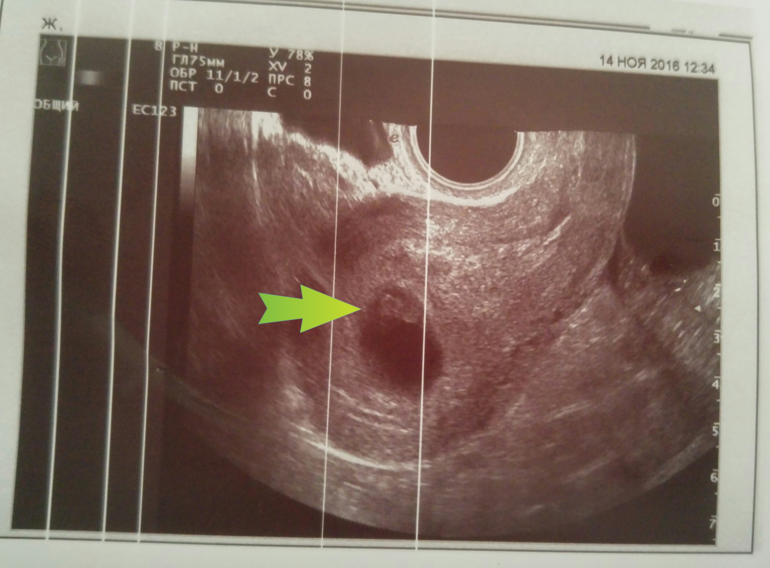

УЗИ в 7 недель

Личный дневникСегодня увидела своего эмбриончика! 9 мм)) дали посмотреть, как у него бьется сердечко! И послушать)) вроде 147 ударов в секунду.

Небольшой тонус, а так все хорошо! Поставили срок 7,5 недель. По факту - ровно 7)) в общем, я счастлива))